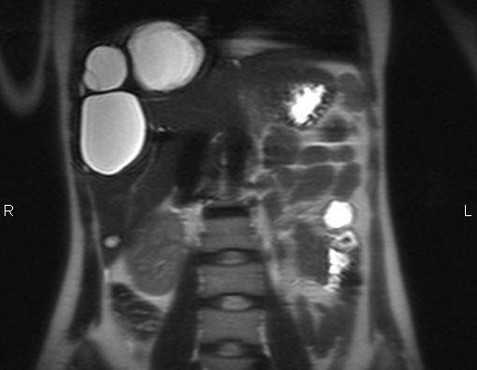

МРТ брюшной полости в аксиальной плоскости. Структура железы неоднородная за счет наличия в области тела кистозных образований (серозная цистаденома), сливающихся между собой (разделенных тонкими перегородками), с достаточно четким и неровным наружным контуром. Содержимое образований характеризуется однородным гиперинтенсивным сигналом на Т2-ВИ.